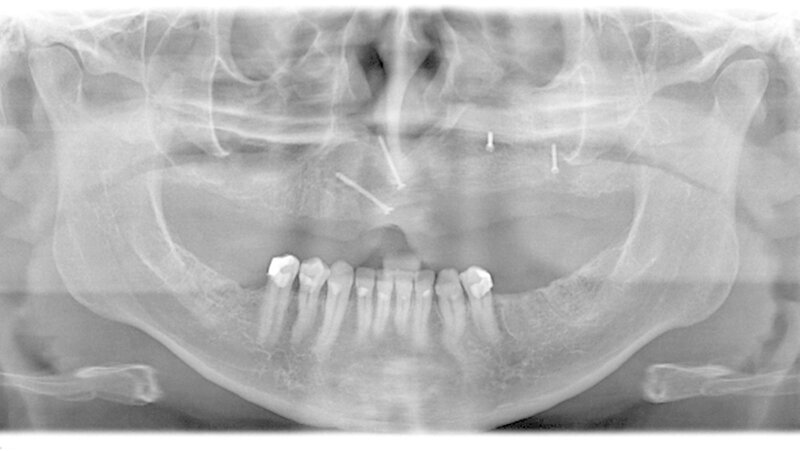

Bereits damals wurde vom Hauszahnarzt eine Entfernung der noch umschriebenen Raumforderung dringend empfohlen. Der Zahnfilm zeigte ein zystisches Geschehen in der Regio 24 und 25 (Abbildung 4). Zur aktuellen weiteren präoperativen Diagnostik wurde eine Computertomografie angefertigt. In den coronalen Schnitten ist die die Mittellinien überschreitende Raumforderung bis zum knöchernen Nasenboden unter Einbezug der linken Kieferhöhle deutlich zu sehen (Abbildung 5a). Man erkennt insbesondere in den sagittalen Schnitten, dass die Raumforderung über zwei Drittel der linken Kieferhöhle beansprucht (Abbildung 5b).

Aufgrund des weit fortgeschrittenen Defekts (Abbildung 6) und der daraus resultierenden insuffizienten prothetischen Versorgung wurde zehn Monate später eine rekonstruktive Operation unter Intubationsnarkose durchgeführt. Hierbei wurde unter Zuhilfenahme eines 5 cm langen monokortikalen Beckenkammspans aus der Crista illiaca (Abbildung 7) eine knöcherne Rekonstruktion des Oberkiefers vorgenommen (Abbildung 8). Als weiterer Schritt ist eine Versorgung mit Implantaten zur Verankerung einer prothetischen Versorgung geplant.